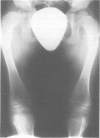

- Temple I. K., Thompson E. M., Hall C. M., Bridgeman G., Pembrey M. E. Kyphomelic dysplasia. J Med Genet. 1989 Jul;26(7):457–461. doi: 10.1136/jmg.26.7.457. [DOI] [PMC free article] [PubMed] [Google Scholar]